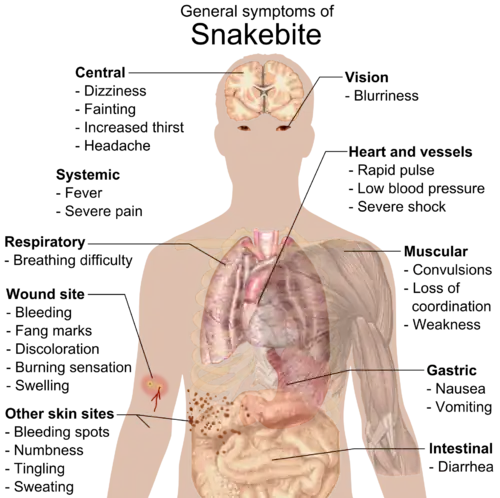

A snakebite is an injury caused by the bite of a snake, especially a venomous snake.[9] A common sign of a bite from a venomous snake is the presence of two puncture wounds from the animal's fangs.[1] Sometimes venom injection from the bite may occur.[3] This may result in redness, swelling, and severe pain at the area, which may take up to an hour to appear.[1][2] Vomiting, blurred vision, tingling of the limbs, and sweating may result.[1][2] Most bites are on the hands, arms, or legs.[2][10] Fear following a bite is common with symptoms of a racing heart and feeling faint.[2] The venom may cause bleeding, kidney failure, a severe allergic reaction, tissue death around the bite, or breathing problems.[1][3] Bites may result in the loss of a limb or other chronic problems or even death.[11][3]

The most common first symptom of all snakebites is an overwhelming fear, which may contribute to other symptoms, and may include nausea and vomiting, diarrhea, vertigo, fainting, tachycardia, and cold, clammy skin.[2][23] Snake bites can have a variety of different signs and symptoms depending on their species.[11]

Most snakebites, from either a venomous or a non-venomous snake, will have some type of local effect.[25] Minor pain and redness occur in over 90 percent of cases, although this varies depending on the site.[2] Bites by vipers and some cobras may be extremely painful, with the local tissue sometimes becoming tender and severely swollen within five minutes.[18] This area may also bleed and blister and may lead to tissue necrosis. Other common initial symptoms of pit viper and viper bites include lethargy, bleeding, weakness, nausea, and vomiting.[2][18] Symptoms may become more life-threatening over time, developing into hypotension, tachypnea, severe tachycardia, severe internal bleeding, altered sensorium, kidney failure, and respiratory failure.[2][18]

Bites by some snakes, such as the kraits, coral snake, Mojave rattlesnake, and the speckled rattlesnake, may cause little or no pain, despite their serious and potentially life-threatening venom.[2] Some people report experiencing a "rubbery", "minty", or "metallic" taste after being bitten by certain species of rattlesnake.[2] Spitting cobras and rinkhalses can spit venom in a person's eyes. This results in immediate pain, ophthalmoparesis, and sometimes blindness.[26][27]

Some Australian elapids and most viper envenomations will cause coagulopathy, sometimes so severe that a person may bleed spontaneously from the mouth, nose, and even old, seemingly healed wounds.[18] Internal organs may bleed, including the brain and intestines,[29] and ecchymosis (bruising) of the skin is often seen.[30]

The venom of elapids, including sea snakes, kraits, cobras, king cobra, mambas, and many Australian species, contains toxins which attack the nervous system, causing neurotoxicity.[2][18][31] The person may present with strange disturbances to their vision, including blurriness. Paresthesia throughout the body, as well as difficulty in speaking and breathing, may be reported.[2] Nervous system problems will cause a huge array of symptoms, and those provided here are not exhaustive. If not treated immediately they may die from respiratory failure.[32]

Venom emitted from some types of cobras, almost all vipers, and some sea snakes cause necrosis of muscle tissue.[18] Muscle tissue will begin to die throughout the body, a condition known as rhabdomyolysis. Rhabdomyolysis can result in damage to the kidneys as a result of myoglobin accumulation in the renal tubules. This, coupled with hypotension, can lead to acute kidney injury, and, if left untreated, eventually death.[18]